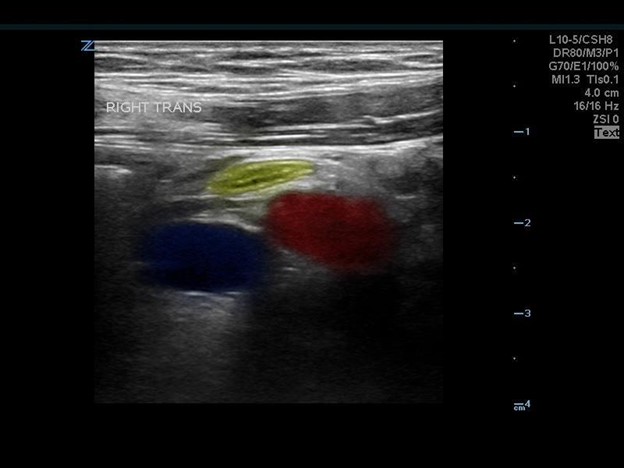

The appendix is most reliably found in the right lower quadrant; the base extends from the proximal cecum and lies anterior to the psoas muscle and the right iliac vessels. Most of the time the distal tip is retrocecal, though the challenge in localization is augmented as the appendix can be pelvically oriented (Images 5 and 6) or directed elsewhere in the abdomen. The normal appendix is tubular, non-peristalsing, compressible, and blind-ended, measuring less than 6 mm. (Image 7)

Image 5. Normal appendix

Image 6. Normal appendix (Yellow: Appendix, Red: Iliac Artery, Blue: Iliac Vein)

Color flow can help delineate the iliac artery and vein from bowel and musculature and should be utilized during the appendix ultrasound. An emphasis should be made to continue using graded compression, as consistent pressure can fully compress a normal appendix making it more difficult to locate. You should save clips and still images with and without compression in multiple planes and apply color flow over the appendix as well.